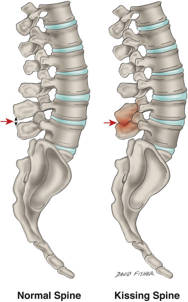

La enfermedad de Baastrup es una causa poco conocida de dolor lumbar. En algunas personas las apófisis espinosas entran en contacto la una con la otra y se produce dolor debido al contacto del hueso contra el hueso. La enfermedad de Baastrup no hace diferencia entre géneros y afecta a personas mayores de 70 años sobre todo.

Con la edad los discos se degeneran, disminuye la altura discal, se producen traumatismos que afectan a los ligamentos y estos se degeneran adelgazándose o incluso rompiéndose, si a estos cambios degenerativos le asociamos un aumento de la lordosis lumbar puede ocurrir que entren en contacto las apófisis espinosas.

Dibujo de la enfermedad de Baastrup